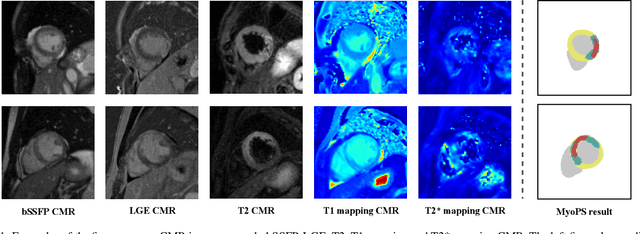

Myocardial pathology segmentation (MyoPS) can be a prerequisite for the accurate diagnosis and treatment planning of myocardial infarction. However, achieving this segmentation is challenging, mainly due to the inadequate and indistinct information from an image. In this work, we develop an end-to-end deep neural network, referred to as MyoPS-Net, to flexibly combine five-sequence cardiac magnetic resonance (CMR) images for MyoPS. To extract precise and adequate information, we design an effective yet flexible architecture to extract and fuse cross-modal features. This architecture can tackle different numbers of CMR images and complex combinations of modalities, with output branches targeting specific pathologies. To impose anatomical knowledge on the segmentation results, we first propose a module to regularize myocardium consistency and localize the pathologies, and then introduce an inclusiveness loss to utilize relations between myocardial scars and edema. We evaluated the proposed MyoPS-Net on two datasets, i.e., a private one consisting of 50 paired multi-sequence CMR images and a public one from MICCAI2020 MyoPS Challenge. Experimental results showed that MyoPS-Net could achieve state-of-the-art performance in various scenarios. Note that in practical clinics, the subjects may not have full sequences, such as missing LGE CMR or mapping CMR scans. We therefore conducted extensive experiments to investigate the performance of the proposed method in dealing with such complex combinations of different CMR sequences. Results proved the superiority and generalizability of MyoPS-Net, and more importantly, indicated a practical clinical application.